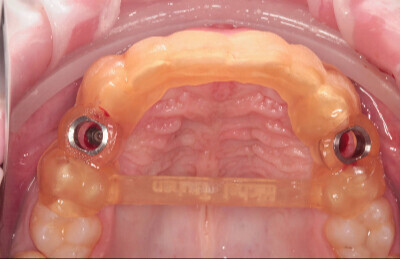

Navigovaná chirurgia, 3 implantátov

Autor práce Dr. Michal Repaši

Zubný technik Vasil Csopej